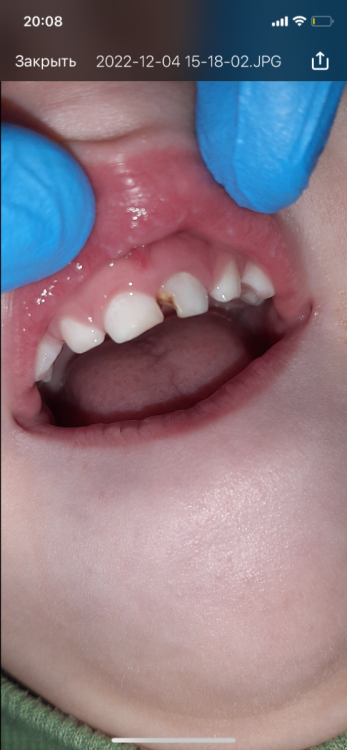

Polina21 Опубликовано 4 декабря, 2022 Поделиться Опубликовано 4 декабря, 2022 Здравствуйте!Ребенку 4года,молочный передний зуб частично разрушен. Были у стоматолога, сказали кариес,еще немного и источится до нерва. Сказали все там чистить и ставить пломбу,но делать под седацией. Хочу услышать ваше мнение судя по снимку Ссылка на комментарий

сирена Опубликовано 5 декабря, 2022 Поделиться Опубликовано 5 декабря, 2022 Правый зуб лечить, левый удалять. Там уже давно дошло всё до нерва , есть периапикальные изменения(в кости). Можно одномоментно под седацией, можно без седации, просто под местной анестезией, как будет вести себя ребёнок. Ссылка на комментарий

IvanK Опубликовано 5 декабря, 2022 Поделиться Опубликовано 5 декабря, 2022 17 часов назад, Polina21 сказал: Здравствуйте!Ребенку 4года,молочный передний зуб частично разрушен. Были у стоматолога, сказали кариес,еще немного и источится до нерва. Сказали все там чистить и ставить пломбу,но делать под седацией. Хочу услышать ваше мнение судя по снимку Здравствуйте Все зависит от ребенка, если доктор сможет договориться, то можно и без . Но С - обычно проще. Была травма переднего зуба? Делали тест на витальность? Ссылка на комментарий